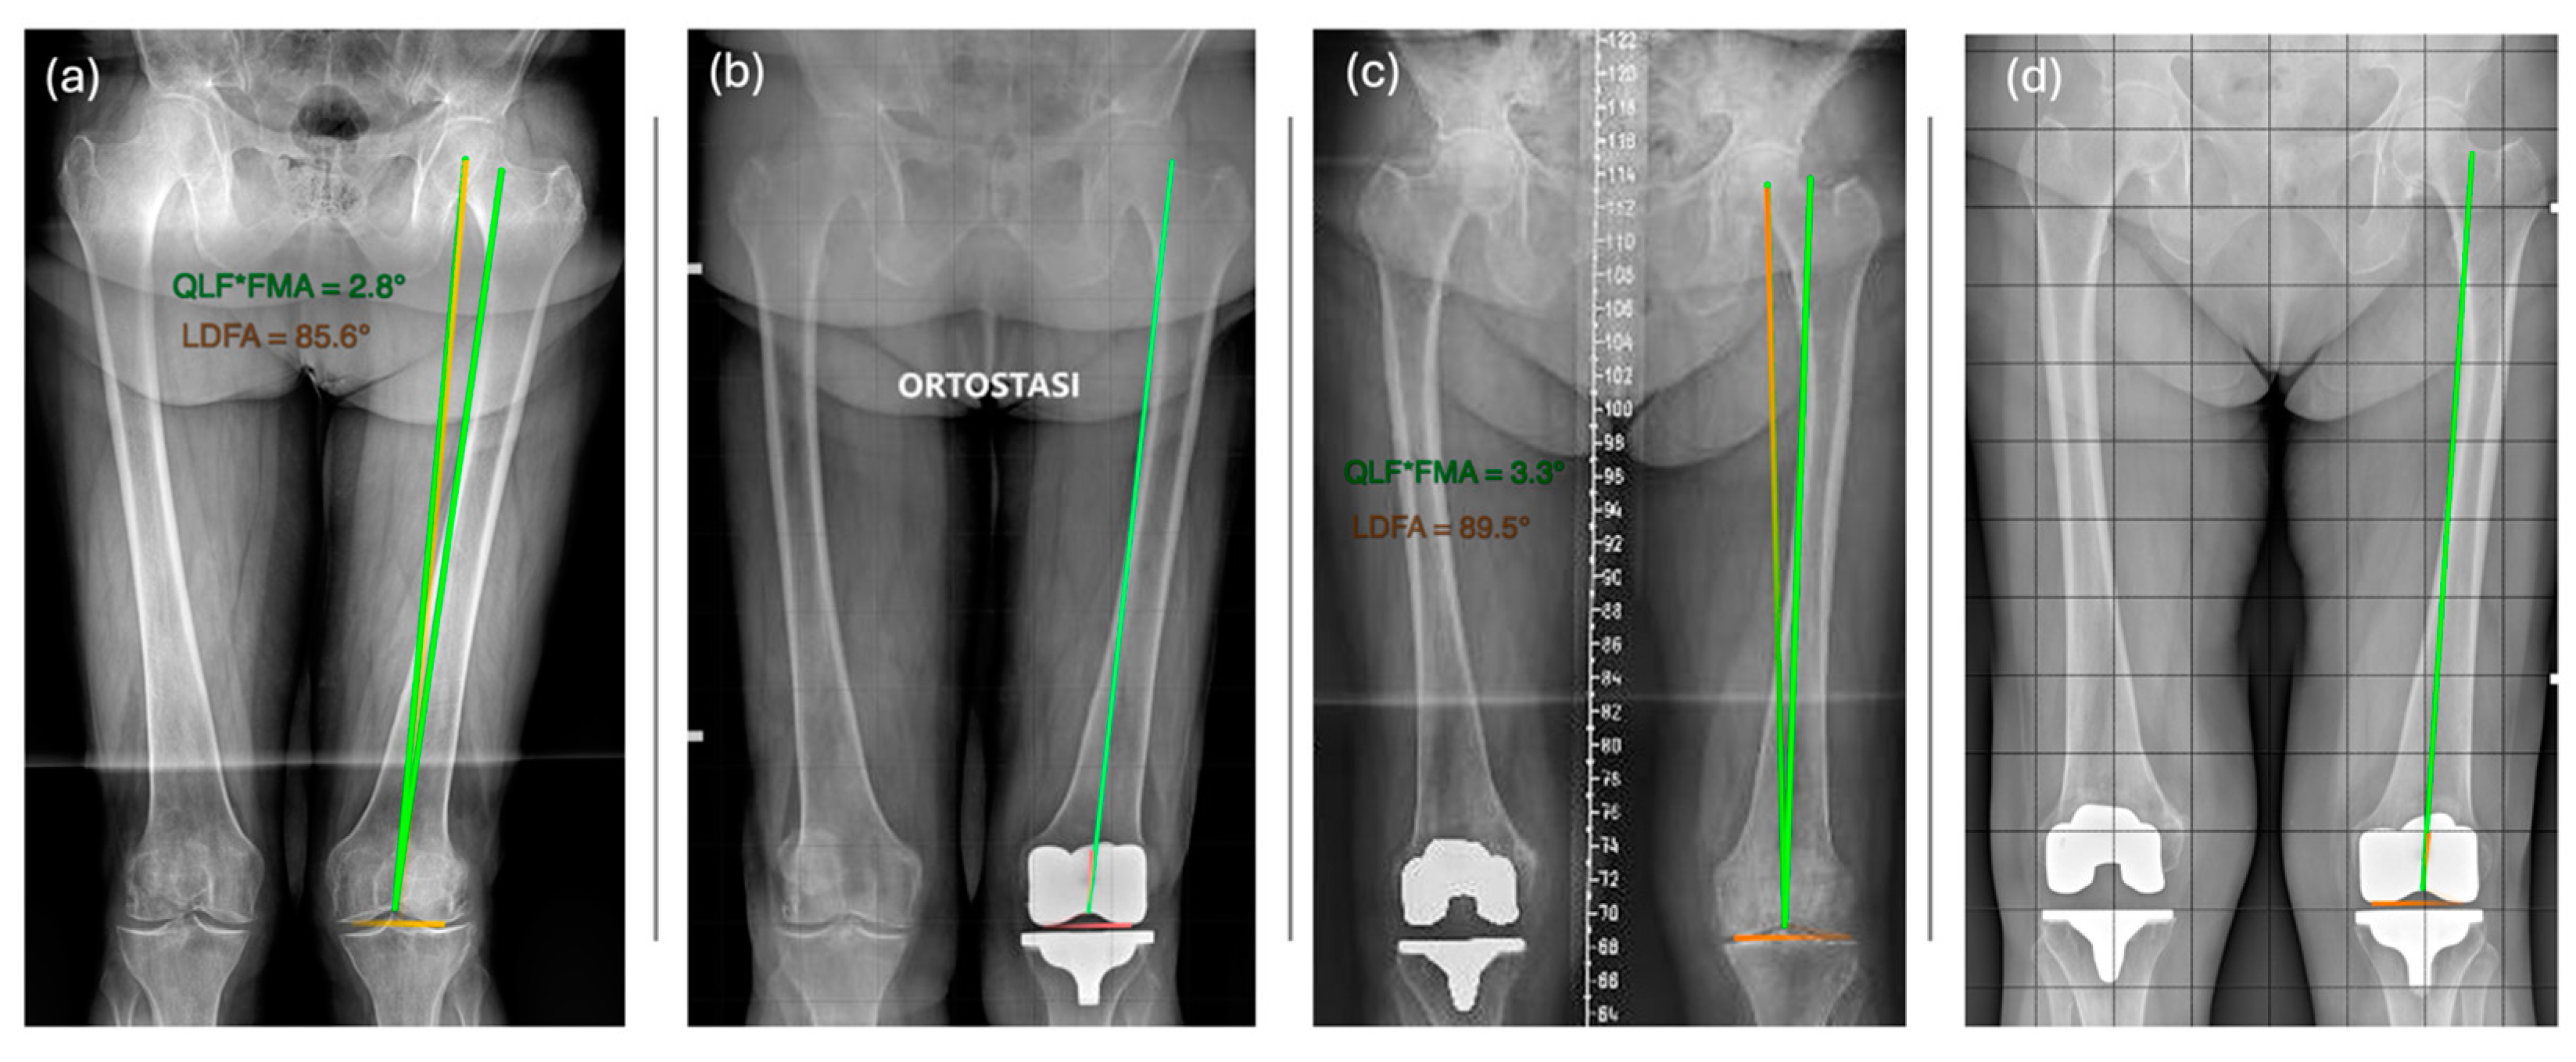

- Patient A has an LDFA of 87° and a QLF^FMA of 2°.

- Patient B also has an LDFA of 87° but a QLF^FMA of 4°.

- For Patient A, the QLF is lateral to the PTA by 1° (x = 2 − (6 − (90 − 87))).

- For Patient B, the PTA is medial to the QLF by 1° (x = 4 − (6 − (90 − 87))).